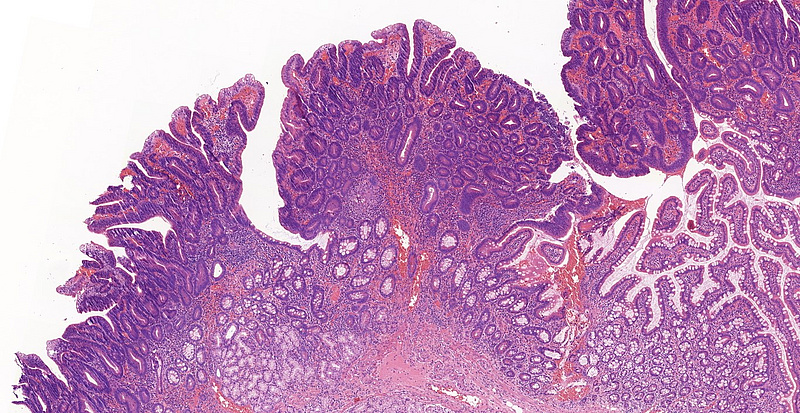

A 60-year-old female patient underwent multiple gastroscopies during the last 5 years because of recurring jaundice. Biopsy samples of the Vater papilla were taken each time, showing tubular or tubulovillous adenomatous growth. In 2021, the lesion was resected in toto with sphincteroplasty. Microscopic examination of this sample revealed tubular and tubulovillous structures, showing signs of low-grade dysplasia (revised Vienna classification category 3) in continuation with normal mucosa [Panels A-D]. Brunner glands were present in the submucosa. Even though the resection margin was free of dysplasia and invasive malignancy not detected, careful follow-up was recommended due to the patient’s history and the recurring nature of the lesion.